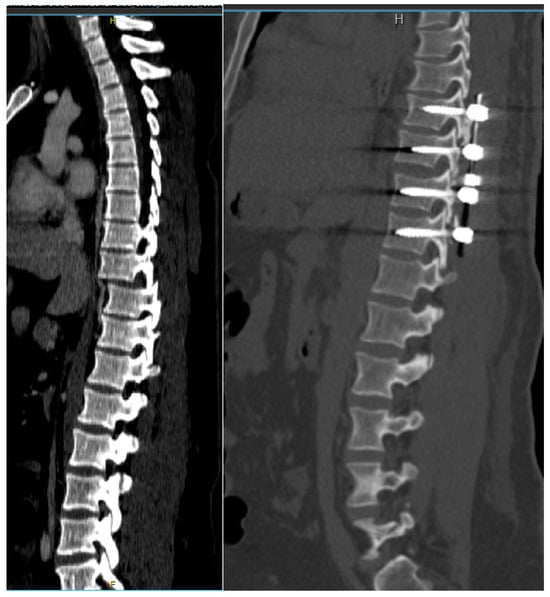

Figure 7.

Computerized tomography scan of thoracic fracture–dislocation (Th9/Th10) successfully and safely reduced using the described technique.